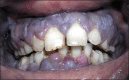

Results: On clinical examination the case presented with features of inflammatory gingival enlargement with presence of local deposits and calculus. Routine blood examination anaemia, thrombocytopenia, leukocytosis with haemoglobin 5.6 gm% and total leukocyte count of 1,12,000 / cu mm suggestive of leukaemia. Myeloperoxidase and leukocyte nonspecific esterase (NSE) special stain were used which showed presence of myeloblasts in the peripheral smear suggestive of acute myelocytic leukaemia. Flow cytometry were done which further helped in interpretation of these cells which showed to be strongly positive for CD45, CD13, CD14, and anti HLADR and moderately positive for CD4, CD34 and Anti MPO confirming to be case of AML-M4 with 57.73% gating.